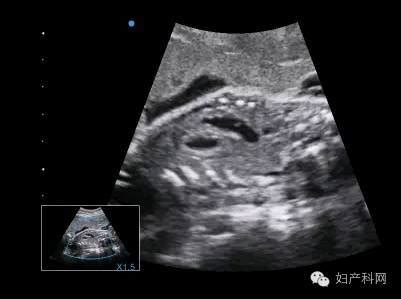

大约在1988年的时候,超声技术已经发展到了可以把一个很小的换能器(声波发射器)插进阴道。这使得探头可以距离胎儿只有几厘米远,并因而得到一个更清晰、具体的图像——声像图。这个探头通过电缆连接到电脑上,井能把图像呈现到显示器上。根据所碰到的组织不同,声波可强可弱,随即探头会接收回波,并将信号传递到电脑,由电脑把这种信号转化为图像。

在怀孕的前12周中,超声检查只能确定怀孕是否在子宫发生,具体怀了几个胎儿,他们是否都还存活以及给出误差不超过96小时的孕龄,而一般不能告诉你胎儿是否健康正常。因此,我们推荐当怀孕16~18周的时候,再进行一次超声检查。在这个时候,绝大多数异常都可以被诊断出来。而在怀孕后期,可能还需要超声诊断一些特别的疾病。早在10年前,美国卫生及公共服务部就制定了27条孕期超声检查的适应指征。